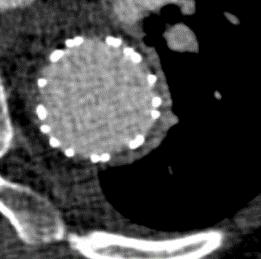

Methods: Consecutive endovascular repairs with adjunctive TES performed for PDAAs between 2022-2023 at two institutions were reviewed. TES was systematically performed to ensure that all grafts were deployed within false lumen-free LZs (Fig 2). Endpoints included TES technical success, defined by the absence of any type Ia or Ib endoleak or entry flow, procedure technical success, aortic true lumen (TL) diameter expansion, major adverse events (MAEs), and 30-day mortality.

Results: Among 121 patients who underwent endovascular repair for PDAAs, 19 (74% male; mean age 57±23 years) underwent adjunctive TES for either acute (10%) or chronic (90%) aortic dissections. Three patients (16%) were treated for genetic-related aortic dissection including two Marfan’s and one Turner’s syndrome. The mean aneurysm sac diameter was 51.9±17.3 mm and median operative time was 175 min [interquartile range, IQR 120-242]. After TES, twenty-one optimized LZs were created. Sixteen distal LZs, including 12 aortic and 4 iliac, were optimized for 11 thoracic endovascular aneurysm repairs (TEVARs), 1 arch device repair, 2 fenestrated and branched endovascular aneurysm repairs (FB-EVARs) and 1 endovascular aneurysm repair (EVAR). Additionally, five optimized proximal LZs were achieved for 3 EVARs and 2 FB-EVARs. TES technical success was 95%. Procedure technical success was 100%, with all grafts and stents deployed as planned. TL diameter increased from 10.9±4.8 mm to 27.5±12.1 mm (P<.001). Median follow-up was 3 months [IQR 0-8]. One patient (5%) had a type Ib entry flow treated with false lumen coil embolization. No MAEs related to TES, or 30-day mortality occurred.